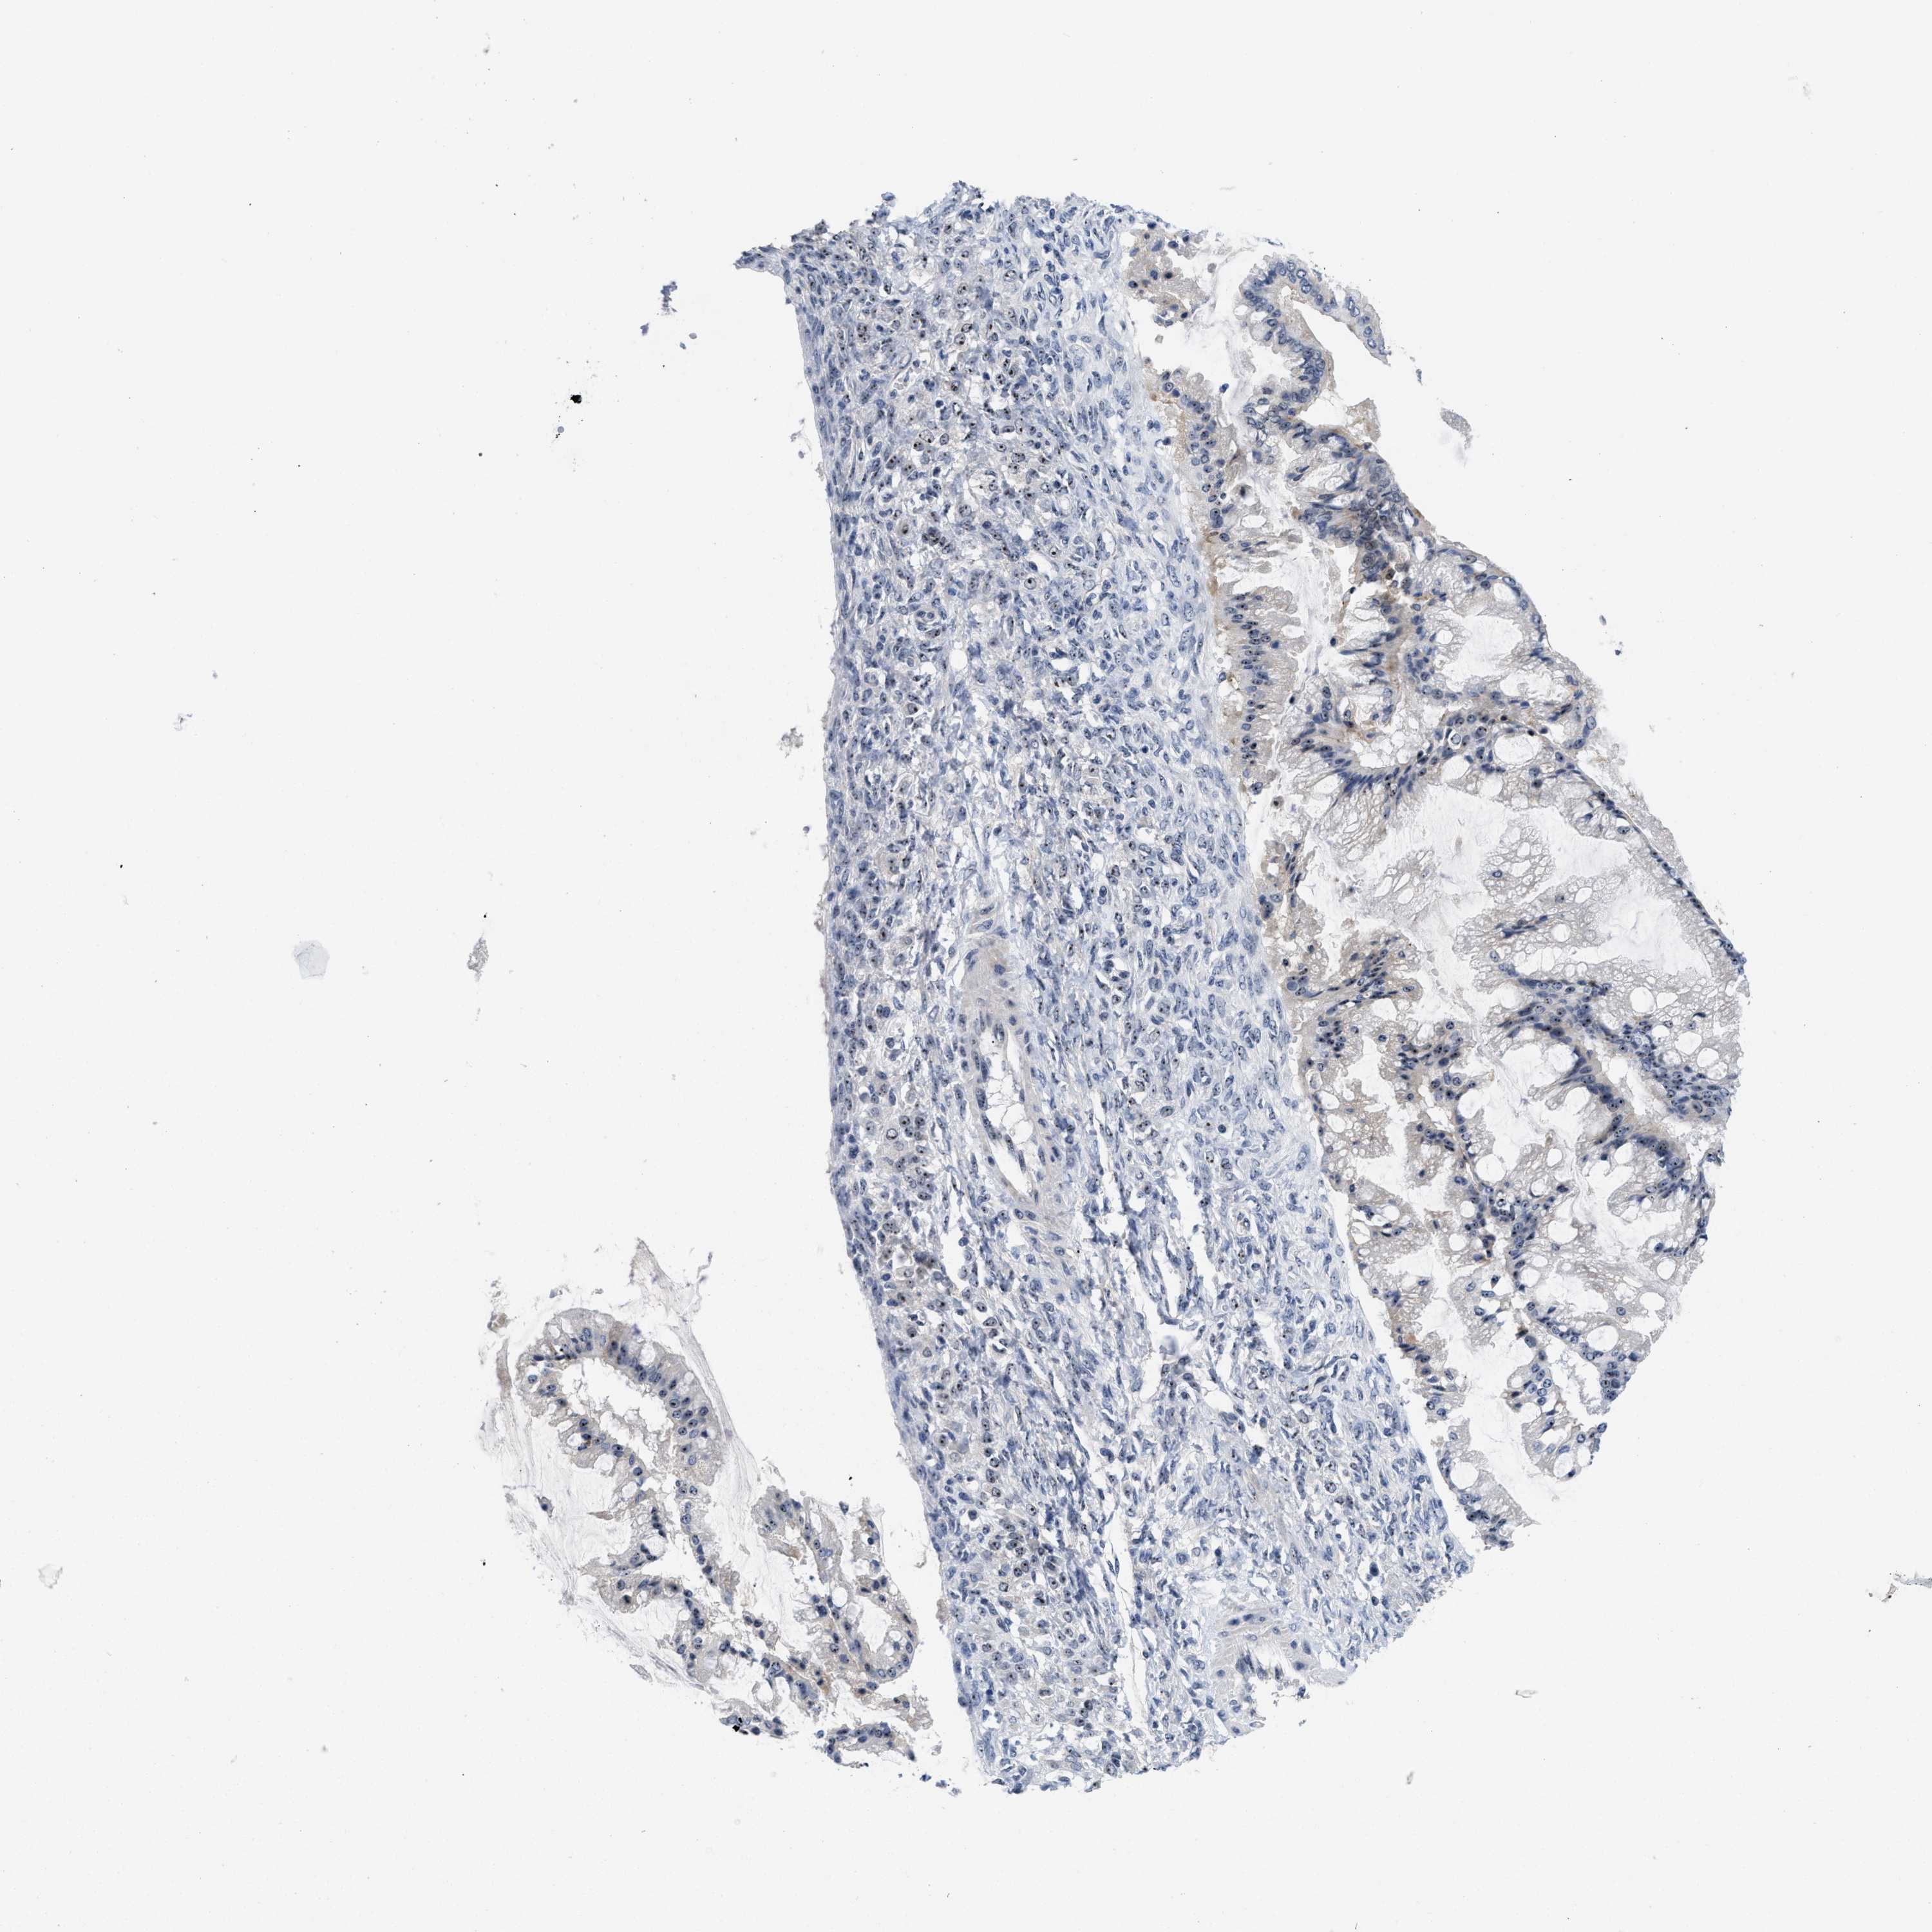

OVARIAN CANCER - Protein expressioni

A mouse-over function shows sample information and annotation data. Click on an image to view it in a full screen mode. Samples can be filtered based on level of antibody staining by selecting one or several of the following categories: high, medium, low and not detected. The assay and annotation is described here.

Note that samples used for immunohistochemistry by the Human Protein Atlas do not correspond to samples in the TCGA dataset.

Antibody stainingi

Antibody staining in the annotated cell types in the current human tissue is reported as not detected, low, medium, or high, based on conventional immunohistochemistry profiling in selected tissues. This score is based on the combination of the staining intensity and fraction of stained cells.

Each image is clickable and will lead to virtual microscopy that enables deeper exploration of all samples and also displays staining intensity scores, fraction scores and subcellular localization as well as patient and tissue information for each sample.

Antibody HPA018472

Antibody HPA021062

Cystadenocarcinoma, serous, NOS

Carcinoma, endometroid

Cystadenocarcinoma, mucinous, NOS

Carcinoma, NOS